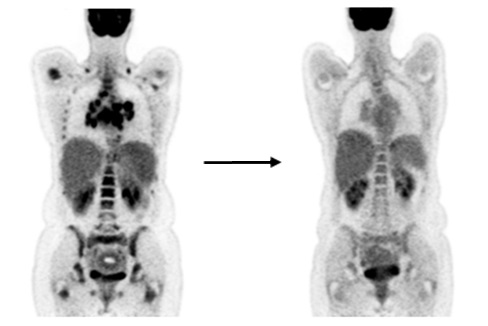

Диагностика лимфомы Ходжкина с помощью ПЭТ и КТ